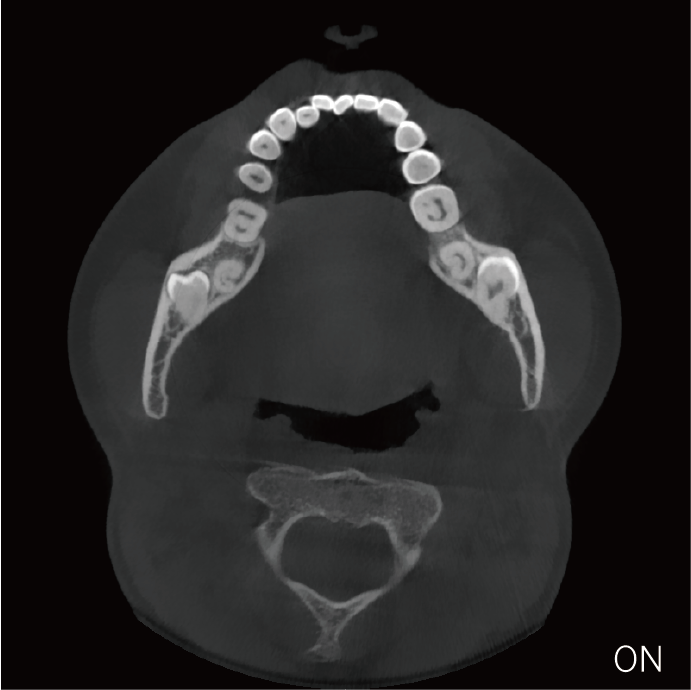

临床样片